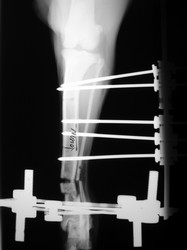

Fijación Externa

PRÁCTICAS CURSO DE FIJACIÓN EXTERNA PERFECCIONAMIENTO.

Híbrido.